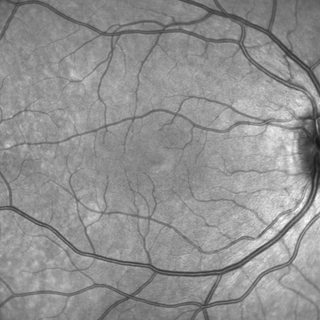

- A Scanning Laser Ophthalmoscopy (SLO) image that gives an overview of the retina.

This library make accessing all these information simple in only a few lines of Java, Kotlin, Mathematica, or any language that can interact with Java. For instance, storing the SLO image as PNG can be done with the following lines

HSFFile hsfFile = new HSFFile(file);

SLOImage slo = hsfFile.getSLOImage();

ImageIO.write(slo.getImage(), "png", output);